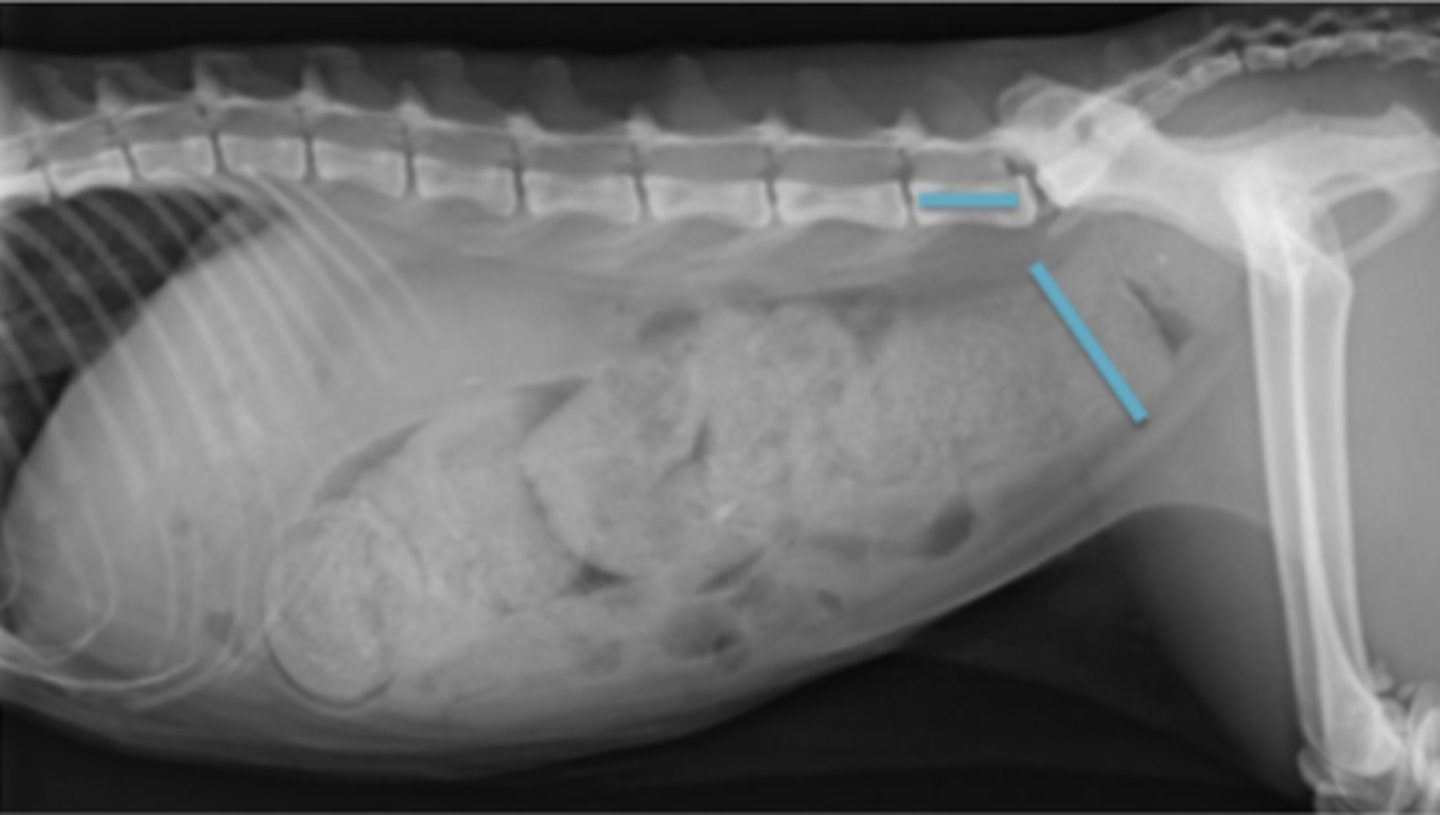

dilatación-torsión gástrica

patología: